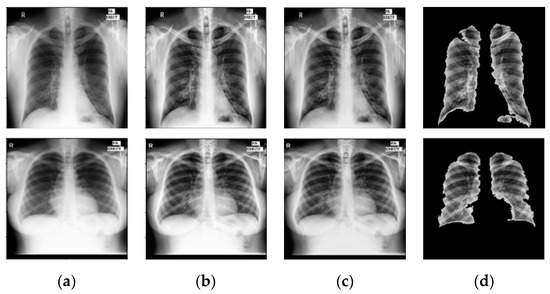

6.2. Prior TB Segmentation